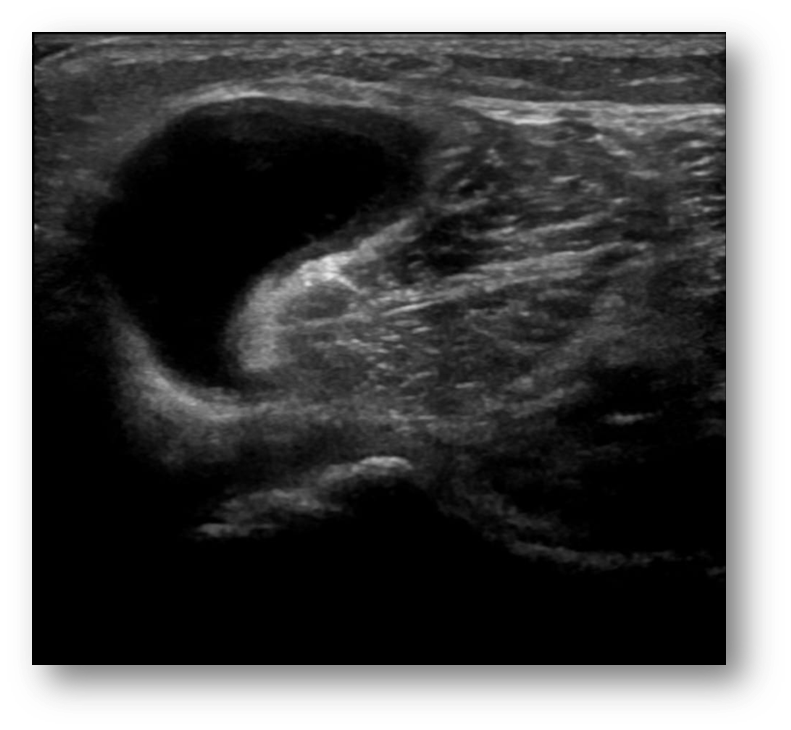

What is this image showing?

bakers cyst